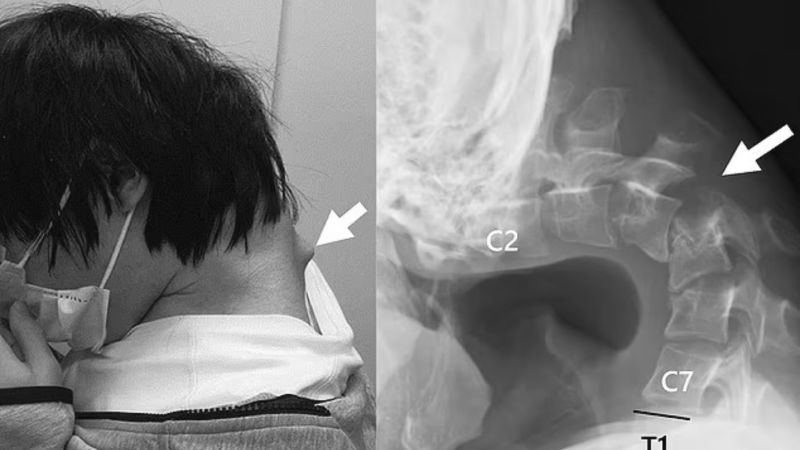

First shared by JOS Case Reports, the photos revealed and warned people that using a phone while the user's head is bent down for prolonged periods of time can result in "dropped head syndrome." X-rays of the 25-year-old Japanese man who developed a bulge extruding from his neck revealed his deformed spine.

(JOS Case Reports)

After a series of scans and multiple failed attempts at getting his neck straight again using collars, the doctors were forced to surgically operate on the man after he developed a distorted vertebra and scar tissue. The patient could only lift his head six months after undergoing several surgical procedures in his neck.